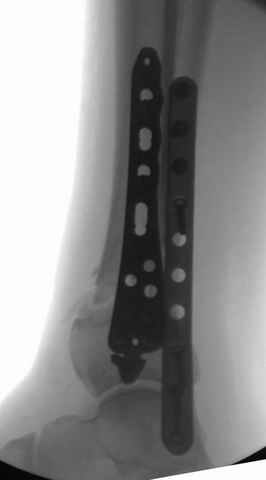

На снимках варианты фиксации малоберцовой:

№ 6-11 при pilon percutaneus fixation

DK> № 6-11 при pilon percutaneus fixation

А если без? Результат был бы хуже?